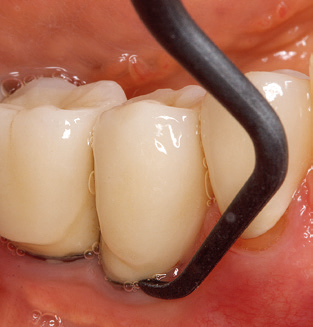

L'attuale piano di lavoro per SPT

Naturalmente, anche i consigli di lavoro per la pulizia delle superfici degli impianti sono indispensabili per SPT nei pazienti dotati di impianti. L'inserto per la pulizia dell'impianto in questo casoi è caratterizzato dal suo design affusolato ed esagonale. Questo design consente una penetrazione leggera e atraumatica nella tasca perimplantare e mostra buone prestazioni di pulizia (Fig. 7).